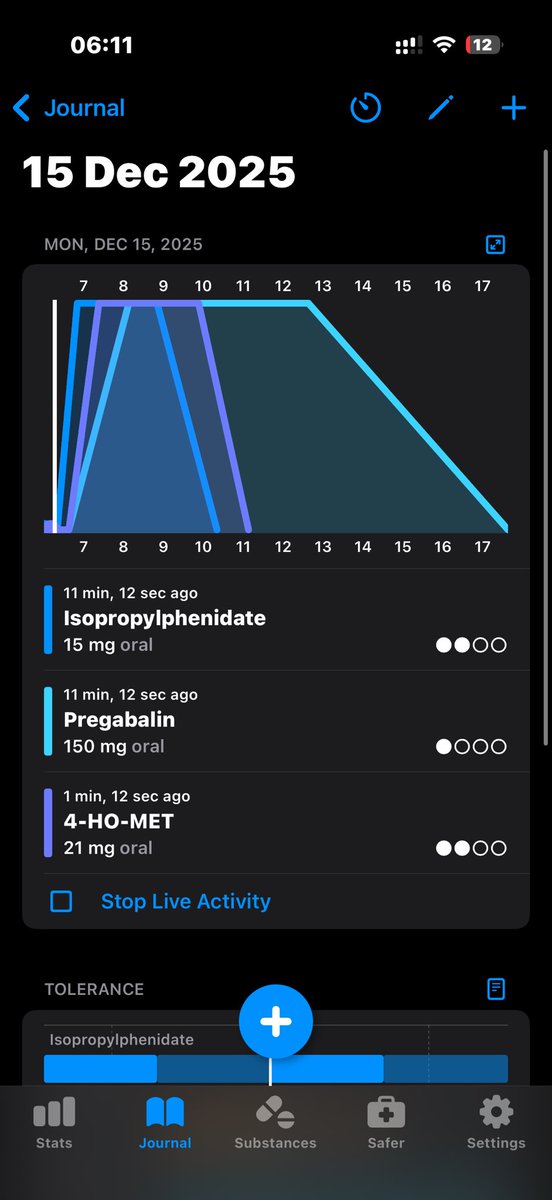

炽烈已极 @AnIncandescence@whitenightX3 journal